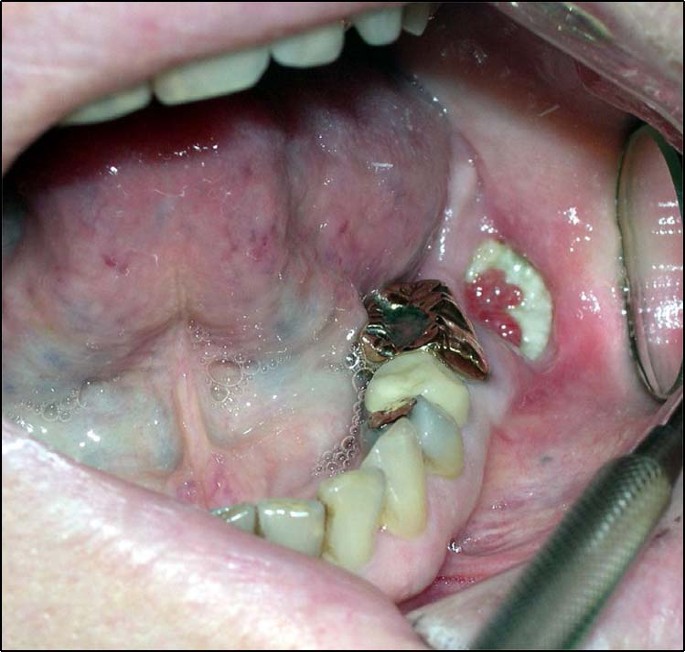

First-generation BPs, for treatment of osteoporosis, were released in 1995. Oral and maxillofacial surgeons noted and published cases of unusual bone exposure in patients in 2003.1,12,13 Dramatic presentation of nonhealing bone after a routine dental extraction, i.e., MRONJ, with exposure of necrotic bone alarmed dental and medical communities and their patients (Fig. 1); though the etiology was slow to be identified as the affected population included osteoporotic patients and patients receiving chemotherapy, high-dose steroids, and BPs.14,15 Management included debridement, removal of bone sequestra, jaw resections, control of infections, and subsequent free-tissue composite reconstruction. Unfortunately, the consequences of ONJ, even when infections were controlled, left many individuals debilitated and with chronically exposed bone. The surgical principle of resecting or debriding until bleeding healthy bone is encountered did not apply to these patients as the impact of the BPs was widespread throughout the jaw bones. Interestingly, osteonecrosis appeared to have a distinct predilection for bones of the head and neck region, particularly the mandible (lower jaw) and maxilla (upper jaw).13,16

Clinical photo of nonhealing bone after a routine dental extraction with exposure of necrotic bone. 67-year-old female with nonhealing extraction site of the lower left second molar (#18). Patient had a history of metastatic breast cancer and was receiving chemotherapy, prednisone, and zoledronate. Unfortunately, 4 months after the extraction, the site was painful with exposed bone and poor healing consistent with medication-related osteonecrosis of the jaw. Normal bone healing after a dental extraction would have shown mucosal coverage within a month